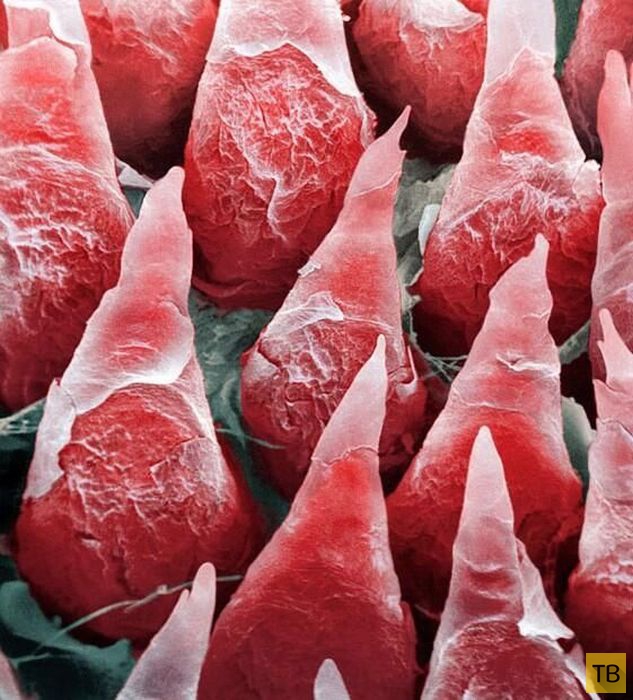

Микроскопическое изображение человеческого языка

Микроскопическое изображение человеческого языка